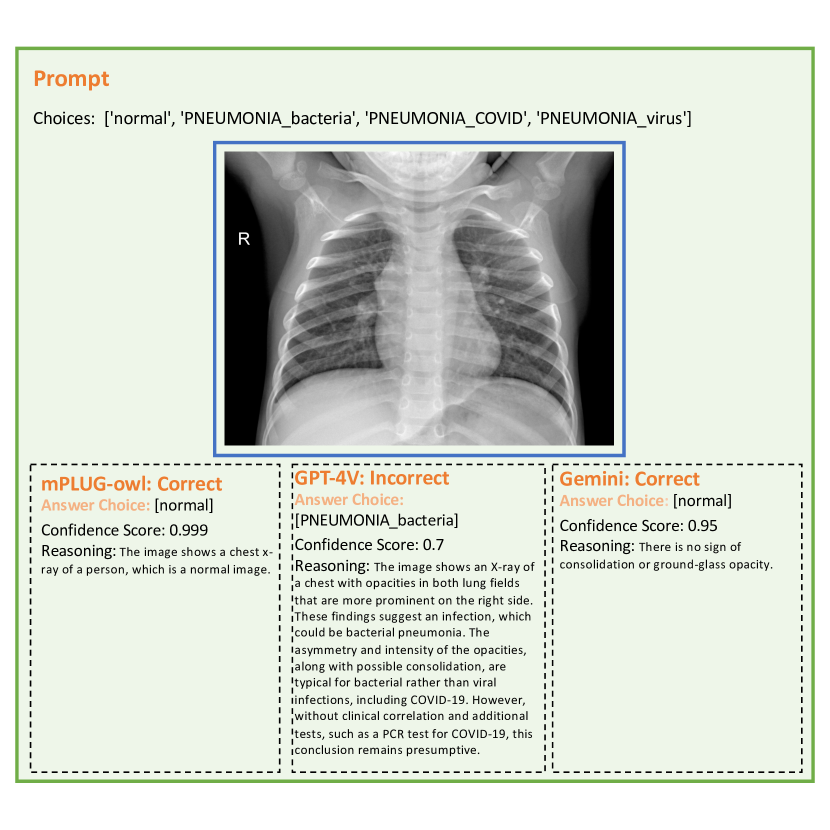

Appendix B Case Demonstration

Here we present cases of zero-shot generalization of MLLMs. While LLMs demonstrate impressive capabilities in capturing salient features of common objects, they encounter significant limitations in comprehending specific visual domains. Please note that we omit the detailed prompt and only category selection space for understanding in the following presentation of case studies. All the models are assigned to provide responses to the same textual prompt as shown in Section 2 and 6.3.